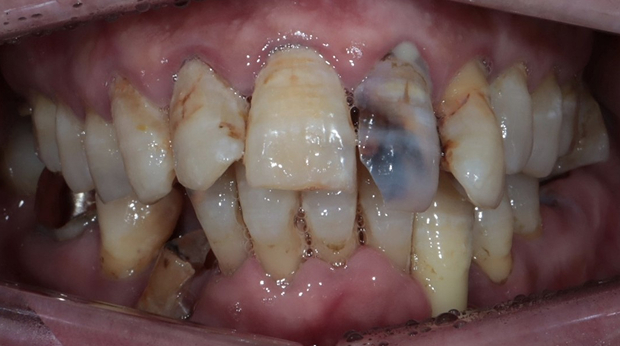

치과 공포증을 해소하여 적절한 치료시기를 놓치지 마세요!

자면서 치료받는, 의식하진정법(수면진정치료)

자고 일어나면, 모든 치료가 끝나 있습니다.